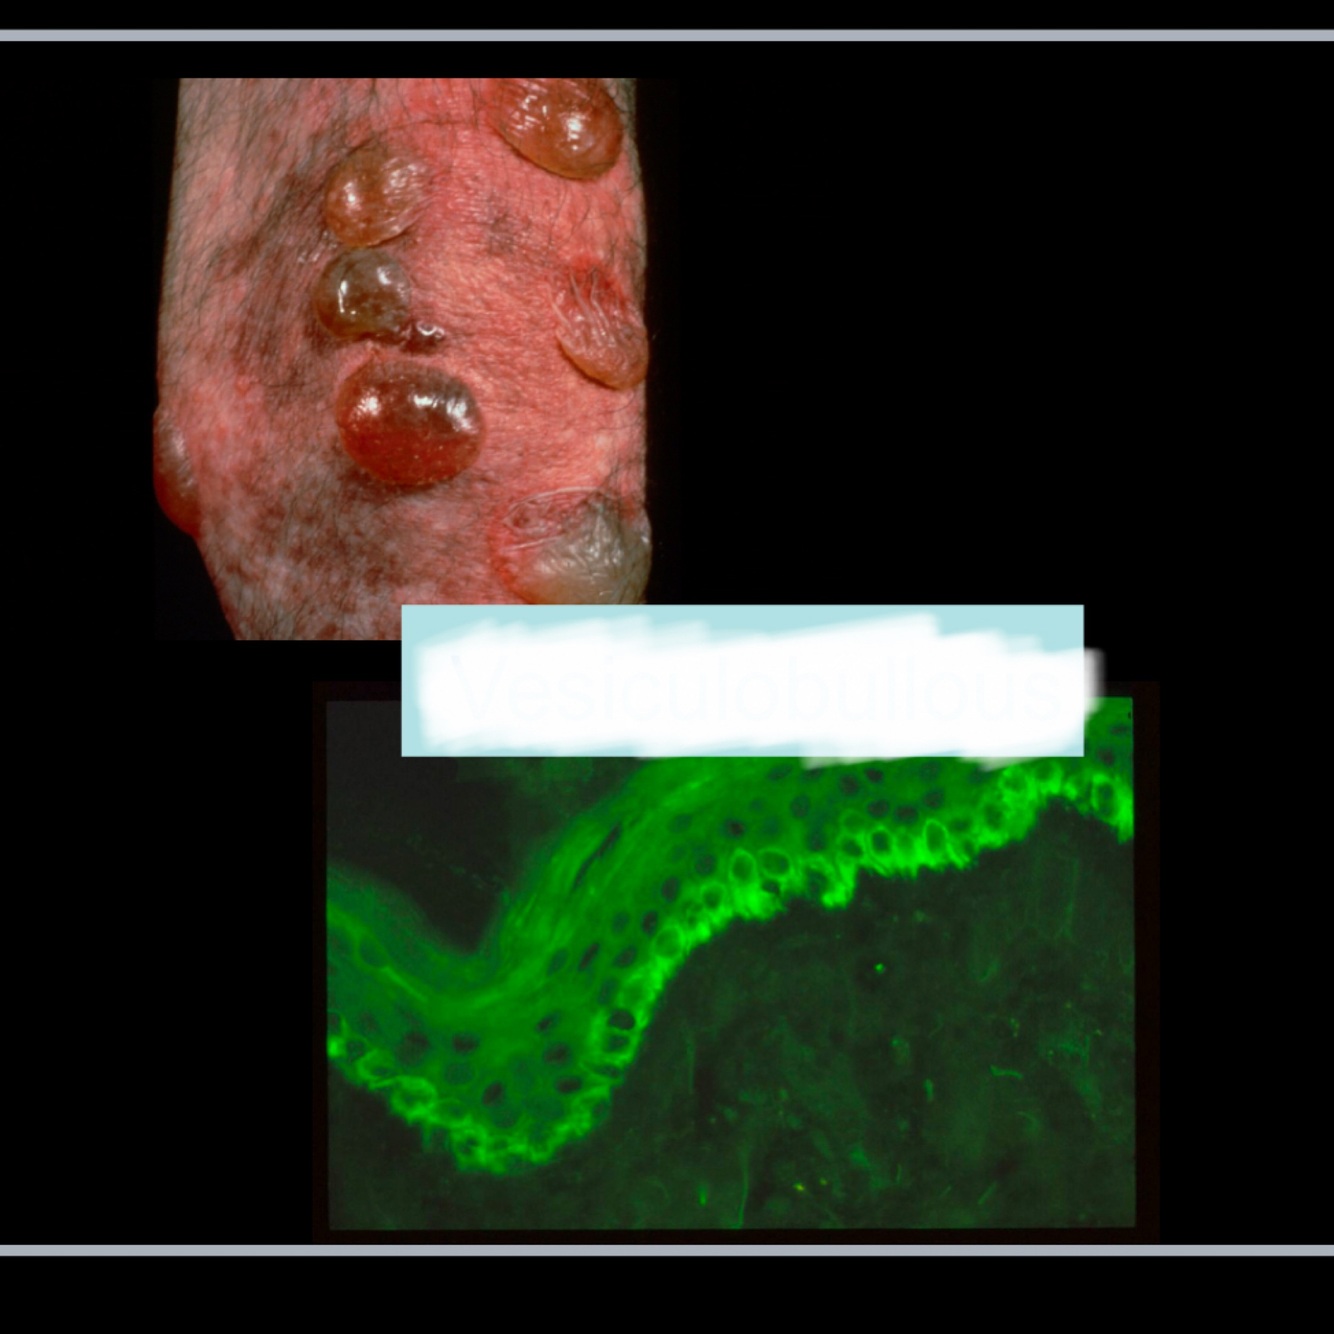

What is this lesion?

A

SCC